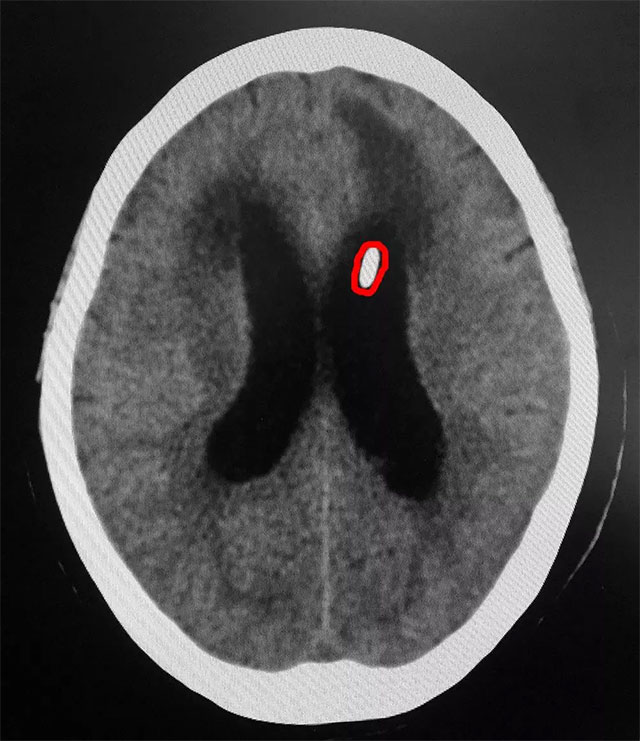

6月22日,上海蓝十字脑科医院神经外科6B病区收治了一位重度脑积水患者。一个月前,患者闫女士(化名)因后交通动脉瘤破裂昏迷,在当地医院进行了手术,术后,患者一直处于昏迷状态,并出现了脑积水等并发症。之后完善相关检查,患者经过CT确诊为交通性脑积水,脑室系统均扩张,患者脑积水情况严重,颅内压更是高达300mmH₂O,达到脑室腹腔分流手术的指征。

▲ 患者置入储液囊后情况较前好转